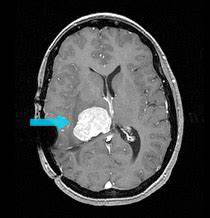

问:脑膜瘤手术之前都检查什么?脑膜瘤怎么判断是良性还是恶性 答: 脑膜瘤 通常是在大脑表面形成的缓慢生长的肿瘤。如果它生长并压在大脑或脊髓上...

如何正确诊断良性脑膜瘤和恶性脑膜瘤?脑膜瘤运动障碍表现为从足部开始,渐至下肢,继而上肢肌力障碍,较后波及头面部,如肿瘤向两侧生长,可出现...

良性脑膜瘤与恶性脑膜瘤的区别?怎么做鉴别诊断?脑膜瘤是一种复杂的脑部肿瘤,起源于脑膜组织。根据肿瘤的生物学行为,脑膜瘤可分为良性脑膜瘤和恶...